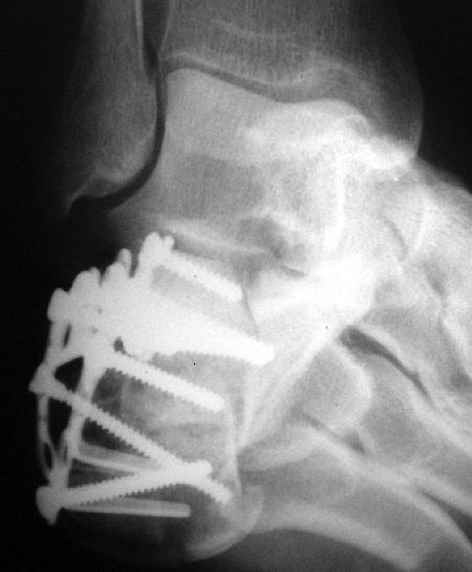

В/суставные переломы пяточной кости у молодых являются показанием к оперативной коррекции, Большой материал накоплен у д-ра Дрягина (Челябинск). В нашем отделении предпочтение отдаем открытой репозиции, при наличии выраженного отека, фликтен и т.д.

Накладываем спицевой дистрактор, позволяющий выхаживать м/ткани и одновременно устранять захождение отломков.

Окончательная фиксация спицами, пяточными пластинами (5) , в последнее время стали применять крючковидные пластины (ДЕОСТ) (6,6a).